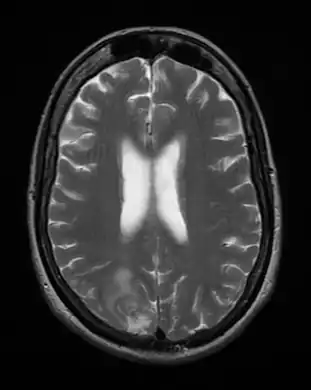

Cerebral toxoplasmosis (with primary involvement in the right occipital lobe)

Cerebral toxoplasmosis

Acute toxoplasmosis is often asymptomatic in healthy adults.[13][14] However, symptoms may manifest and are often influenza-like: swollen lymph nodes, headaches, fever, and fatigue,[15] or muscle aches and pains that last for a month or more. It is rare for a human with a fully functioning immune system to develop severe symptoms following infection. People with weakened immune systems are likely to experience headache, confusion, poor coordination, seizures, lung problems that may resemble tuberculosis or Pneumocystis jiroveci pneumonia (a common opportunistic infection that occurs in people with AIDS), or blurred vision caused by severe inflammation of the retina (ocular toxoplasmosis).[15] Young children and immunocompromised people, such as those with HIV/AIDS, those taking certain types of chemotherapy, or those who have recently received an organ transplant, may develop severe toxoplasmosis. This can cause damage to the brain (encephalitis) or the eyes (necrotizing retinochoroiditis).[16] Infants infected via placental transmission may be born with either of these problems, or with nasal malformations, although these complications are rare in newborns. The toxoplasmic trophozoites causing acute toxoplasmosis are referred to as tachyzoites, and are typically found in bodily fluids.[17][18]